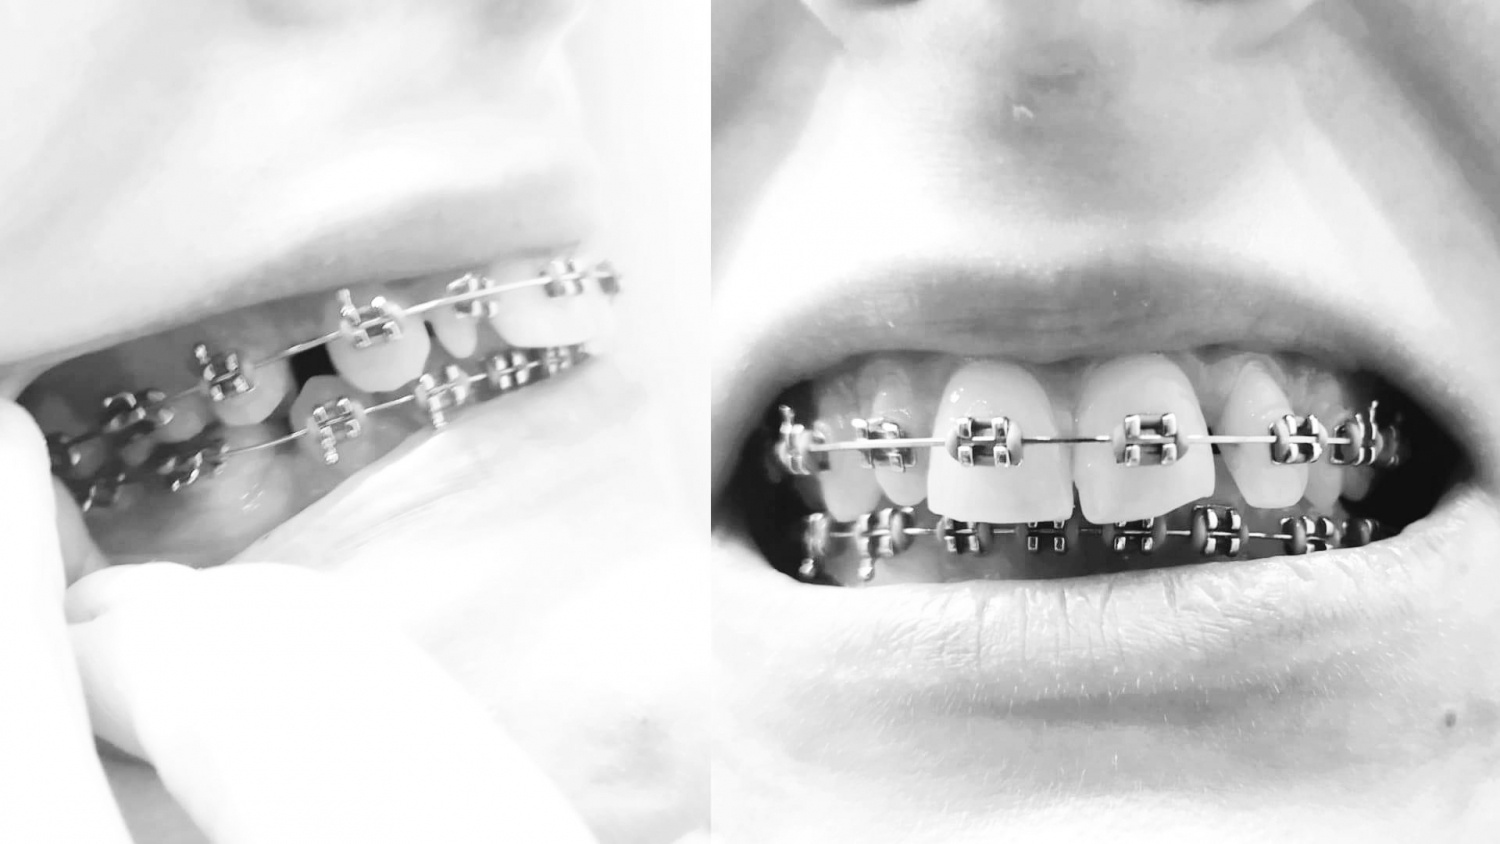

Wrzucam kilka zdjęć. Niestety te, na których się uśmiecham jest garstka.